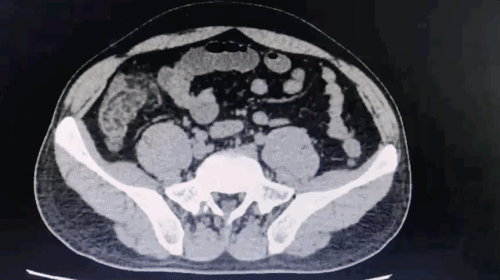

进一步查腹部 CT :

病例一:患者腹部 CT

据 CT 检查所示:盲肠肠壁水肿,脂肪间隙模糊,盲肠壁多个囊袋状突起,其内高密度影(粪石)。阑尾自回盲部向盆腔延伸,腔内可见粪石及积气,但周围无明显炎性渗出表现。